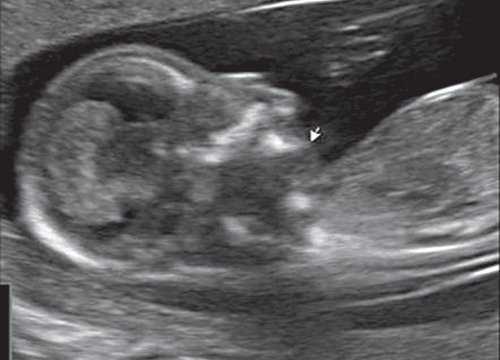

При эхографии в срок 13 недель 3 дня фетометрические параметры плода соответствовали гестационной норме, толщина воротникового пространства составила 1,5 мм; длина костей носа - по 2,5 мм. При трансвагинальном сканировании были обнаружены: затылочное энцефалоцеле размерами 7,4х3,5х3,7 мм (рис. 1), полидактилия кистей (рис. 2), увеличенные кистозно-измененные почки: правая - 28,5х21,3 мм; левая - 26,4х18,7 мм (рис. 3). Объем амниотической полости был нормальным для данного срока.

Синдром Меккеля. Диагностика и прогноз при синдроме Меккеля